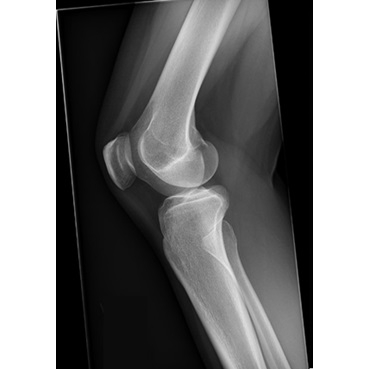

The patient reported acute onset of right lateral knee pain after being slide-tackled during a soccer match five days earlier. She experienced a varus force to her knee as she went for the ball. She reported a sensation of "popping out" at the lateral aspect of her knee at the time of injury. She stated that she had a visible deformity noted to the lateral inferior aspect of her right knee, which was self-resolved by the time she presented to a local ED for initial evaluation. She did not recall exactly how or when it reduced. She was unable to bear weight immediately after the injury. In the ED, radiographs were obtained Case Photo #1 Case Photo #2 Case Photo #3 Case Photo #4 which were negative for acute fracture or dislocation. The patient did not recall the diagnosis, but was recommended a compression wrap, crutches, and analgesics. She was advised to follow up with Sports Medicine. She presented to the Sports Medicine clinic with continued right lateral knee pain with weight-bearing, knee instability, and right anterolateral ankle pain. She reported minimal knee or ankle swelling. She denied symptoms of catching, clicking, locking, skin changes, or lower extremity paresthesias. She had no prior history of injury to the right knee.

Inspection of the right knee revealed mild soft tissue swelling around the proximal fibula, with no deformity or ecchymosis. There was tenderness to palpation at the fibular head, proximal tibiofibular joint, and lateral joint line. She had active range of motion from 0 to 135 degrees, with pain in terminal flexion and extension. Strength was 5/5 with resisted knee extension and 4/5 with resisted knee flexion, limited by pain. On provocative testing, there was lateral knee pain with modified Apley and McMurray tests. Thessaly was not completed due to pain. Additionally, there was pain with varus stress testing, without instability. Lachman, anterior drawer, and posterior drawer tests were deferred due to significant pain and guarding. On neurovascular assessment of the right lower extremity, she had intact sensation to light touch, and skin was warm and well-perfused, with intact pedal pulses.